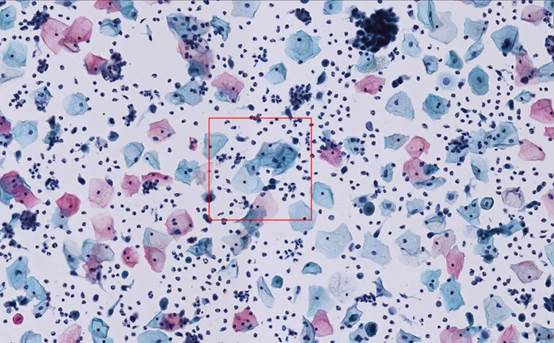

▲ 未明確診斷意義的非典型鱗狀細胞(ASCUS)

▲ 高級別鱗狀上皮內病變細胞(HSIL)

▲ 低度鱗狀上皮內病變細胞(LSIL)

▲ 霉菌